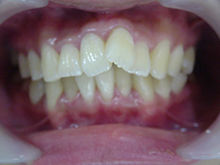

セ ラ ミ ッ ク ク ラ ウ ン

内面には金属を使用し、外面にセラミックを築成するタイプで、従来多くがこの方法で治療されていました。